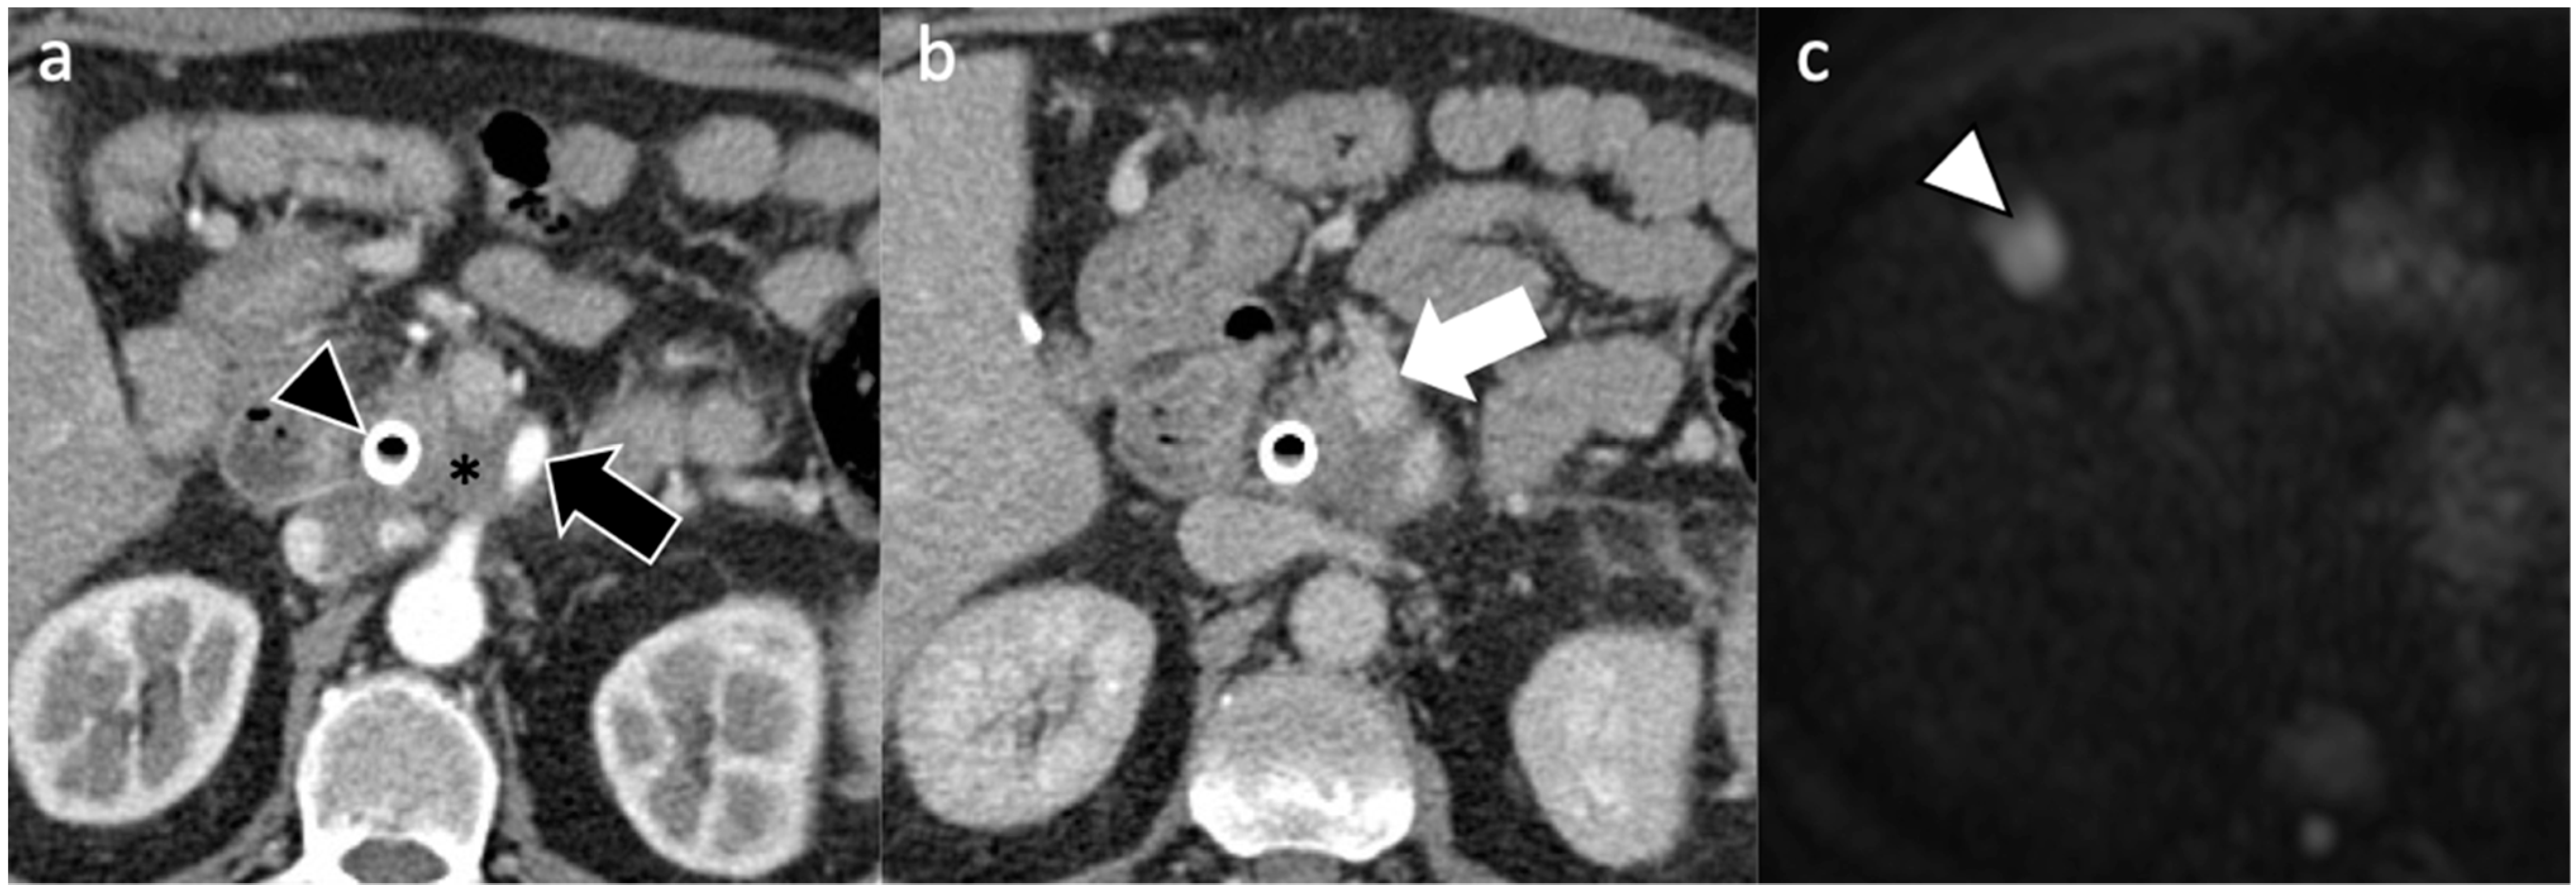

| Ultrasound |

| Computed Tomography |

| Magnetic Resonance Imaging |